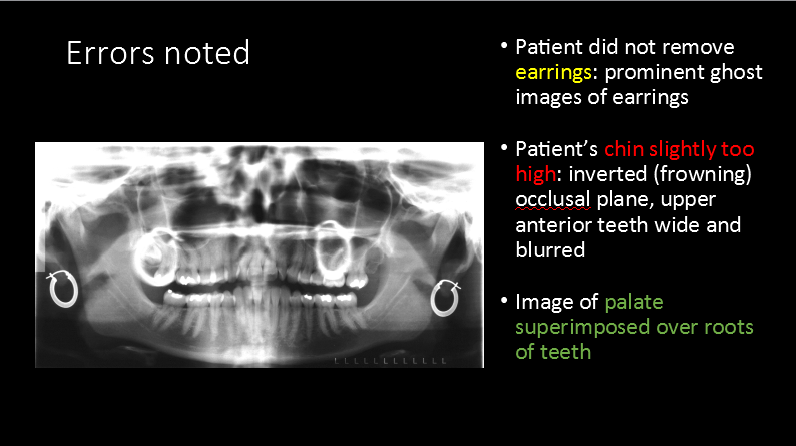

What is the most prominent error depicted in positioning of the patient by the radiographer?

A. Chin a bit too far down

B. Chin a bit too high up

C. Head too far forward

D. Head too far back